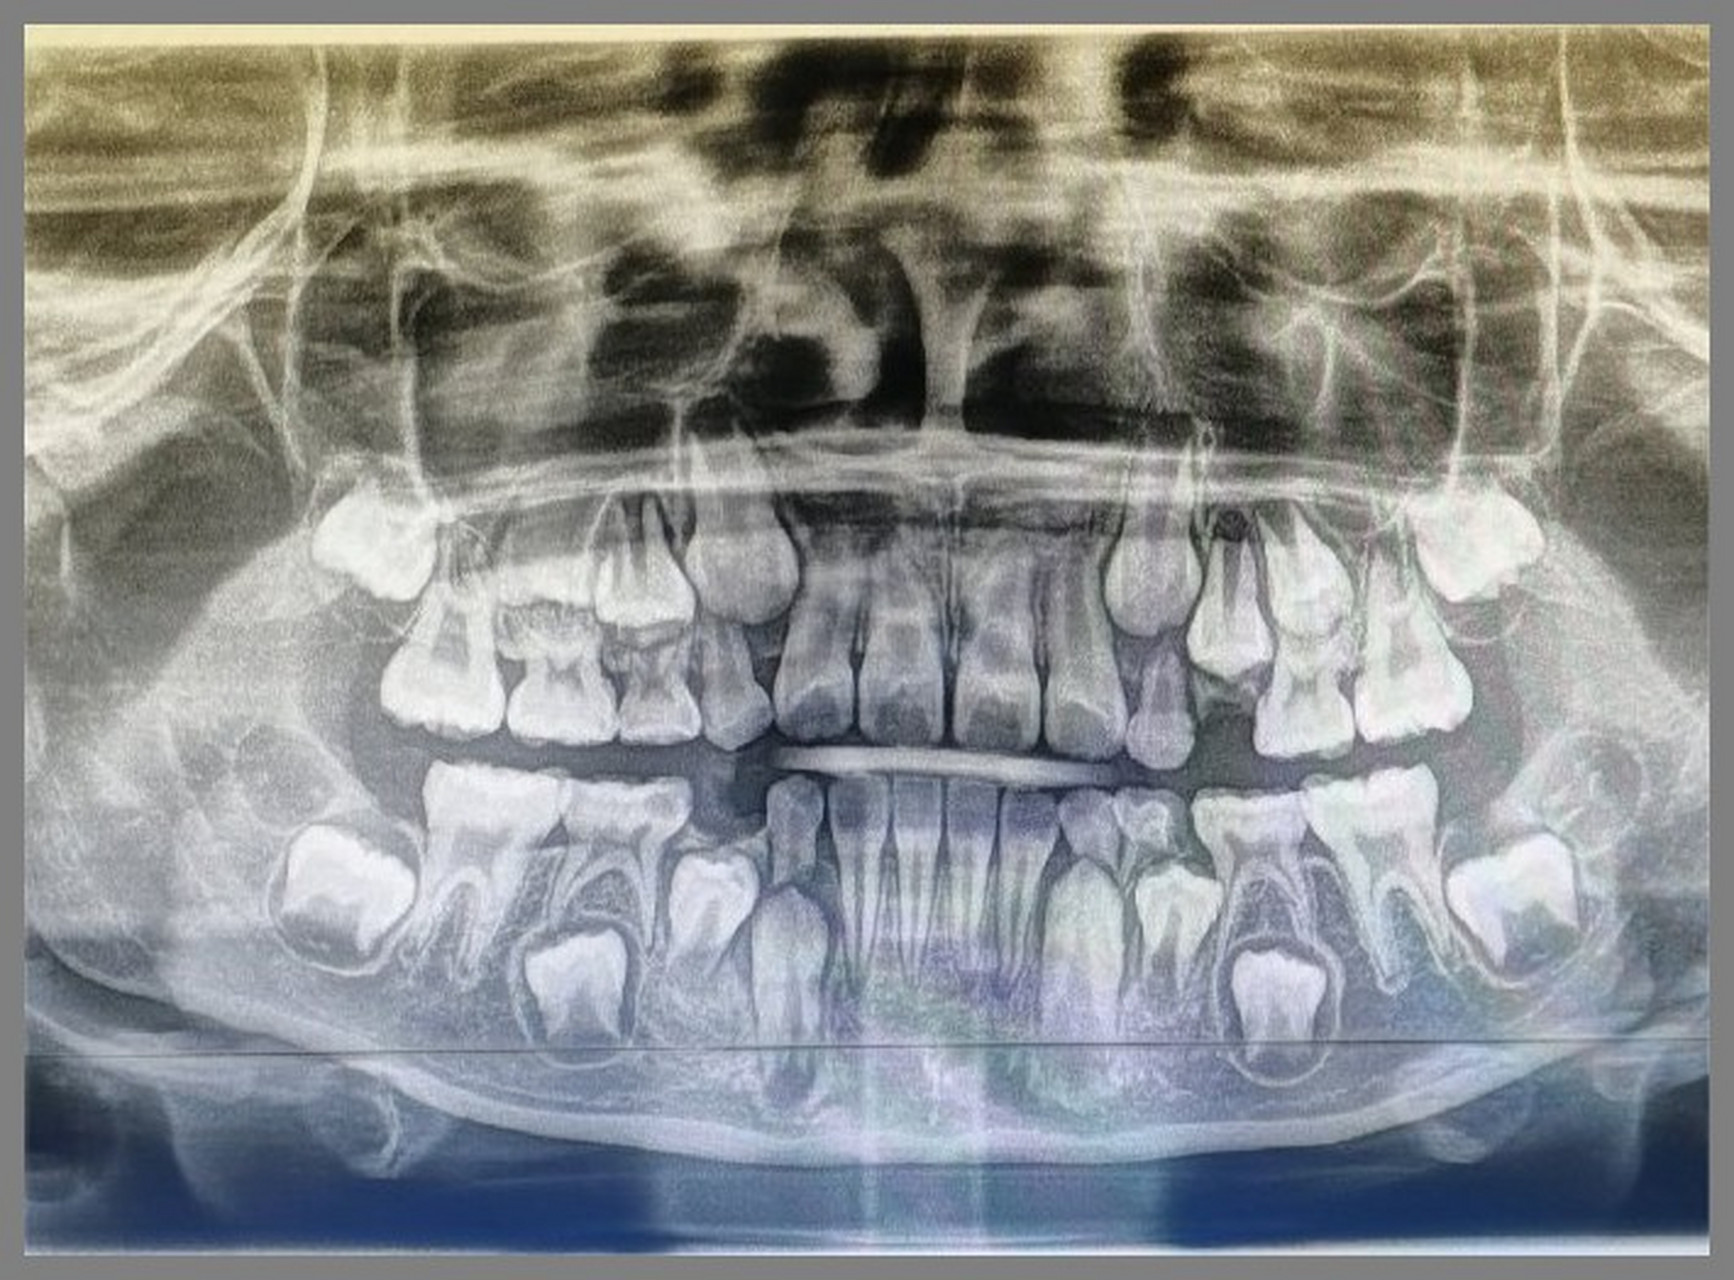

替牙期儿童拍摄全景牙片的意义这个孩子发现有多生牙和牙胚缺失

图片尺寸690x379